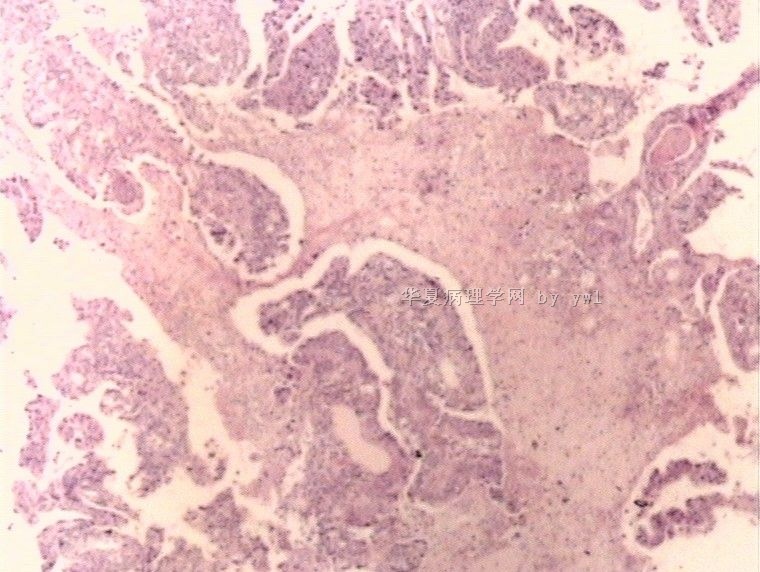

腺鳞癌?

姓    名: ××× 性别:   年龄:  39岁

标本名称:  宫颈活检

简要病史:  同房出血3次,tct HSIL

考虑:原位腺癌,小灶性区域有鳞状上皮向间质内浸润,考虑有鳞状细胞癌结构。

• 腺鳞癌?图3

图3